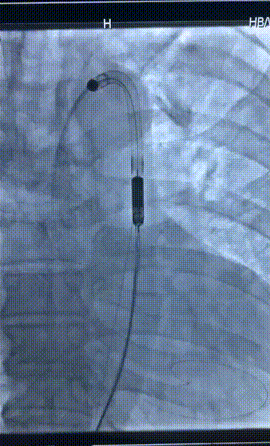

董念国教授团队经全方面评估和多学科会诊后,决定为患者实施经皮心室辅助装置植入手术,改善患者血流动力学。手术采用微创介入方式,顺利经股动脉入路,沿导丝将泵血装置送入左心室,部分替代心脏泵血功能,维持患者血液循环。手术过程顺利,患者平稳转至ICU。

D-Omniheart 植入过程

D-Omniheart植入左心室影像